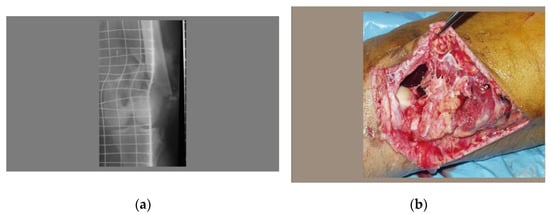

2.2. Second Case—Severity of Disease